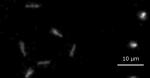

物質中のアルファ線飛跡のリアルタイム画像化に成功~アルファ線内用療法など,様々な研究分野への応用に期待~早稲田大学,東北大学,名古屋大学 UPDATE:2023.05.26 (3年前) | 記事カテゴリー:ニュース 早稲田大学,東北大学,名古屋大学の研究グループは,高分解能放射線イメージング検出器を開発し,放射線の一種であるアルファ線が物質中を飛んでいる様子(飛跡)を短時間間隔の連続画像(リアルタイム画像)として可視化することに成功したと発表した。 東北大学 -TOHOKU UNIVERSITY-世界初 物質中のアルファ線飛跡のリアルタイム画像化に成功 ~アルファ線内用療法...https://www.tohoku.ac.jp/japanese/2023/04/press20230427-01-alpha.html【本学研究者情報】 〇未来科学技術共同研究センター准教授 吉野 将生研究室ウェブサイト 【発表のポイント】 世界で初めて物質中のアルファ線の飛跡をリアルタイムで画像化することに成功 新しい高分解能放射...